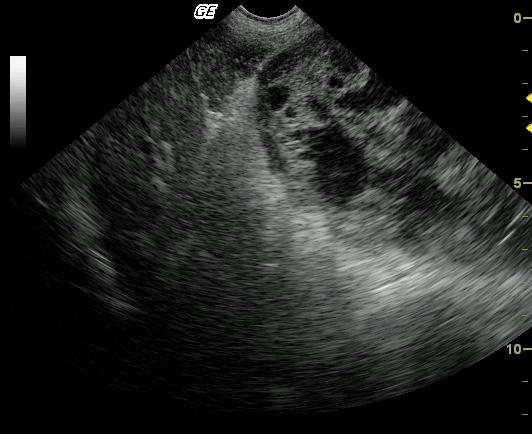

Large cavitated mass with bordering inflammation and suspect omental and mesenteric adhesions. Neoplasia, either benign or malignant arising from a regional soft tissue structure, mesentery or omentum is primarily suspected. Also considered are inflammatory, infectious (parasitic?), granulomatous, hematoma.

A large, well-encapsulated, cavitated and septated mass is present within the peritoneal cavity. The mass is bordered by echogenic omentum and mesentery, which may be adhered. The origin of the mass is not apparent on these images.